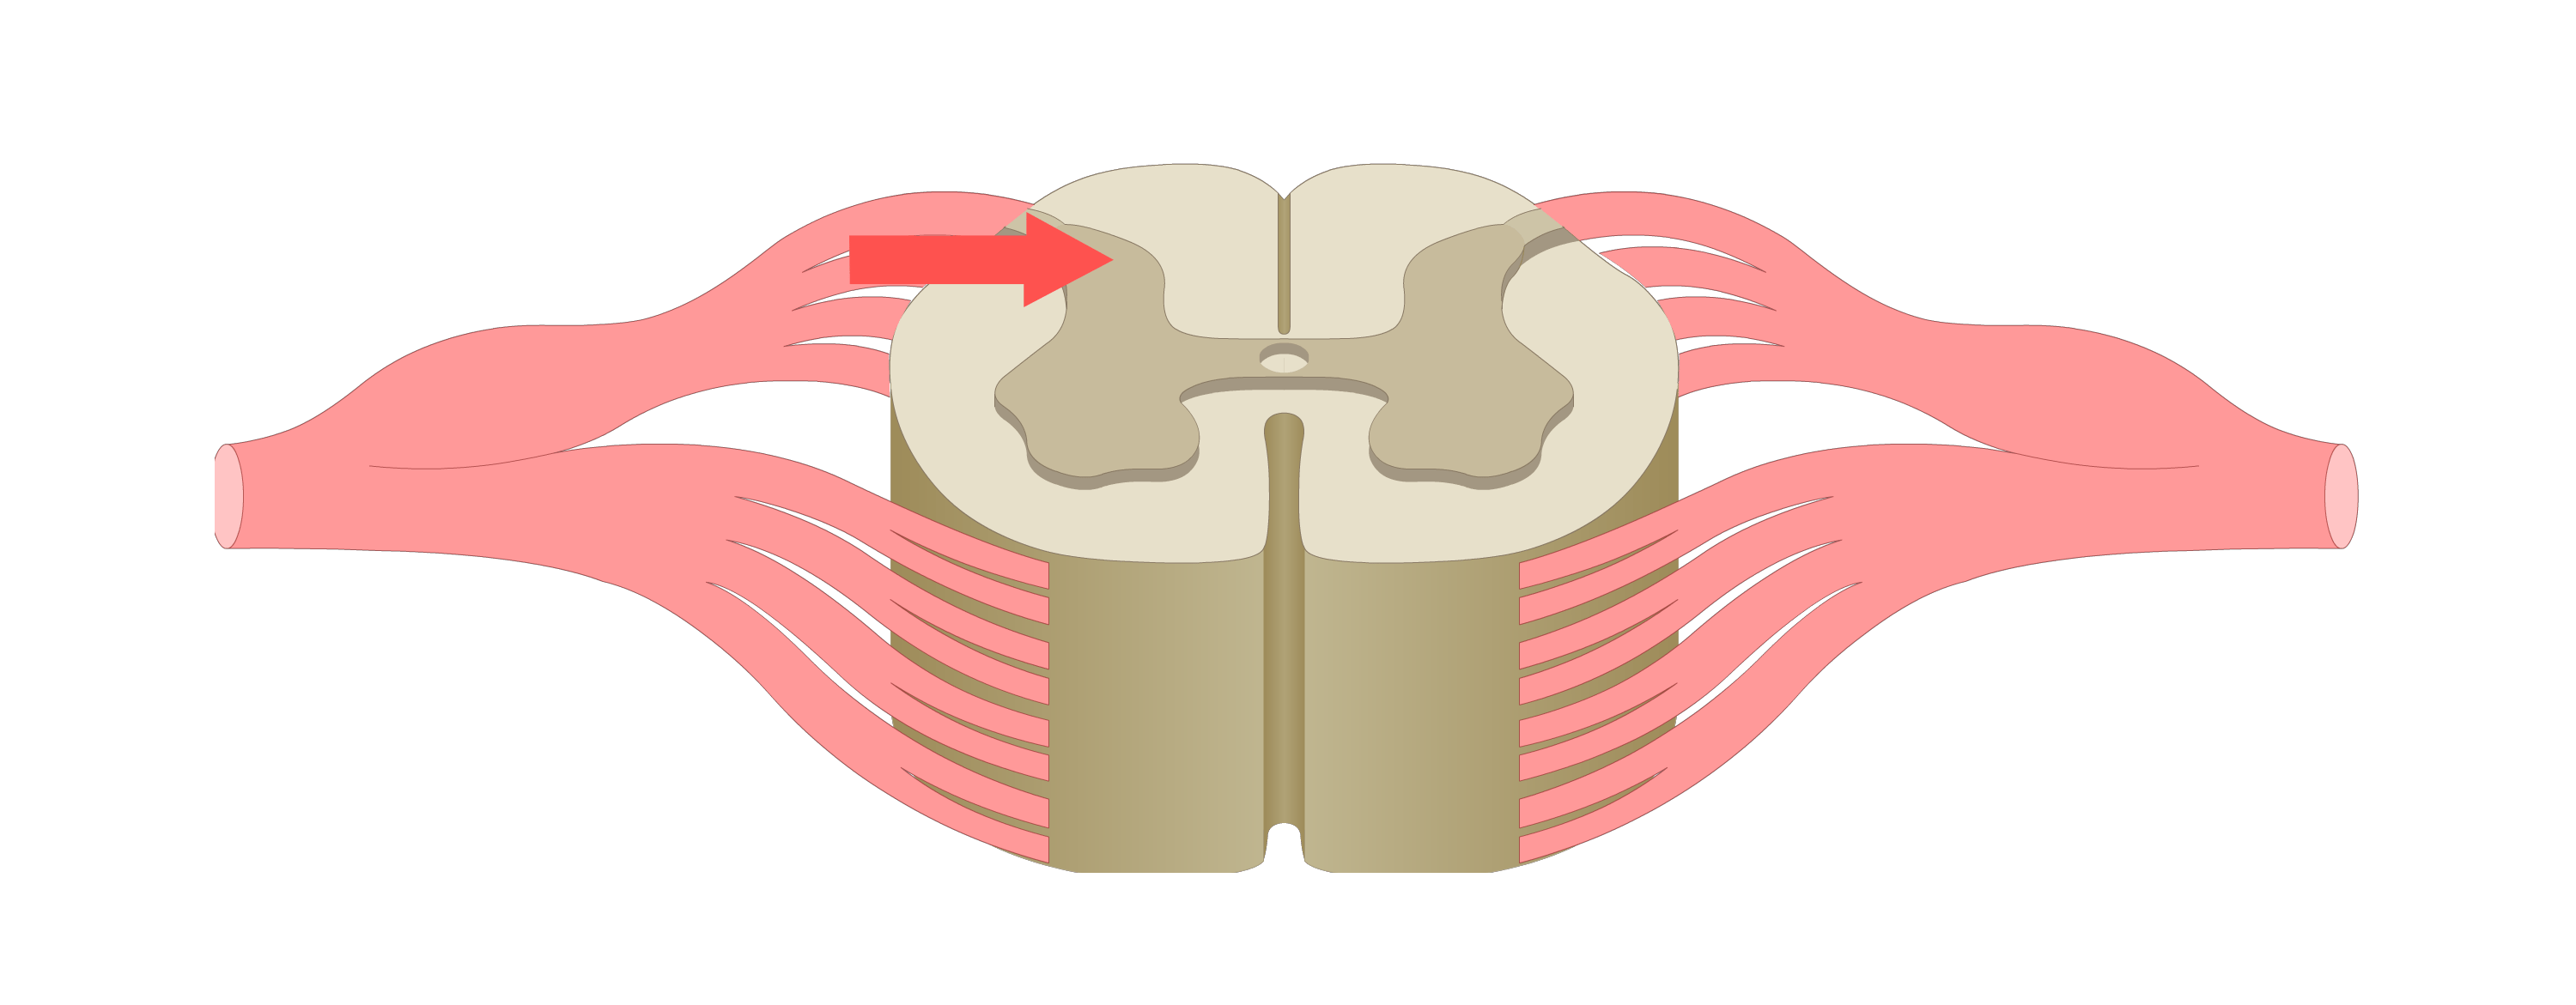

motor tracts

sensory tracts

afferent neuron

carries sensory action potential from receptor to CNS

efferent neuron

carries motor action potentials from integration center to effector organ

control/integration center

single/multiple synapses bw sensory & motor neurons; always in CNS